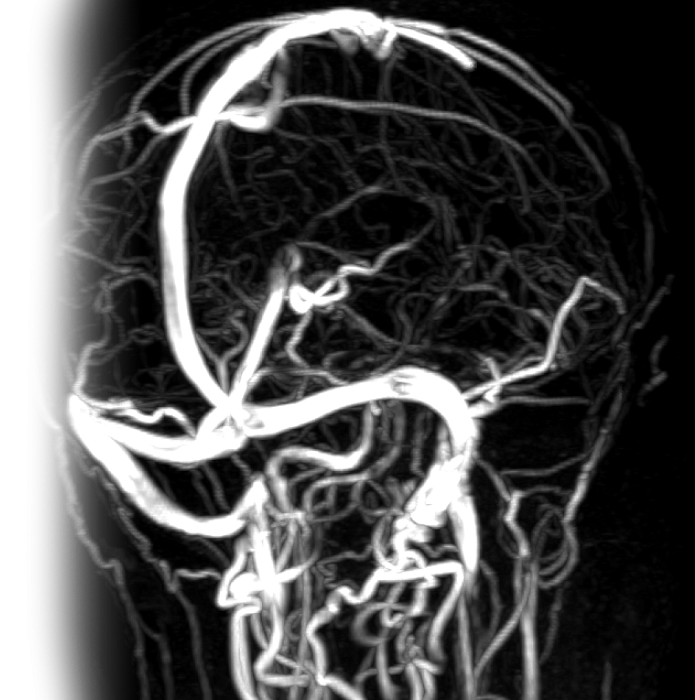

МР ангиография артерий и вен головного мозга

МР бесконтрастная ангиография артерий и вен головного мозга – важный метод исследования, который позволяет оценить состояние артерий, вен и венозных синусов головного мозга.